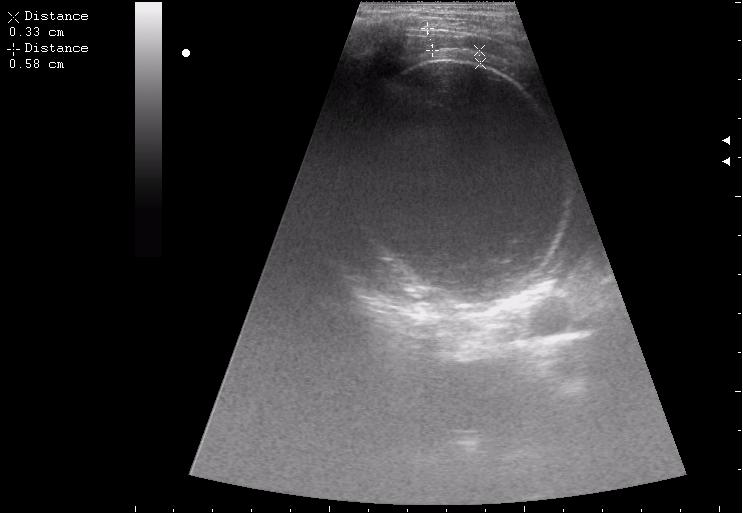

после